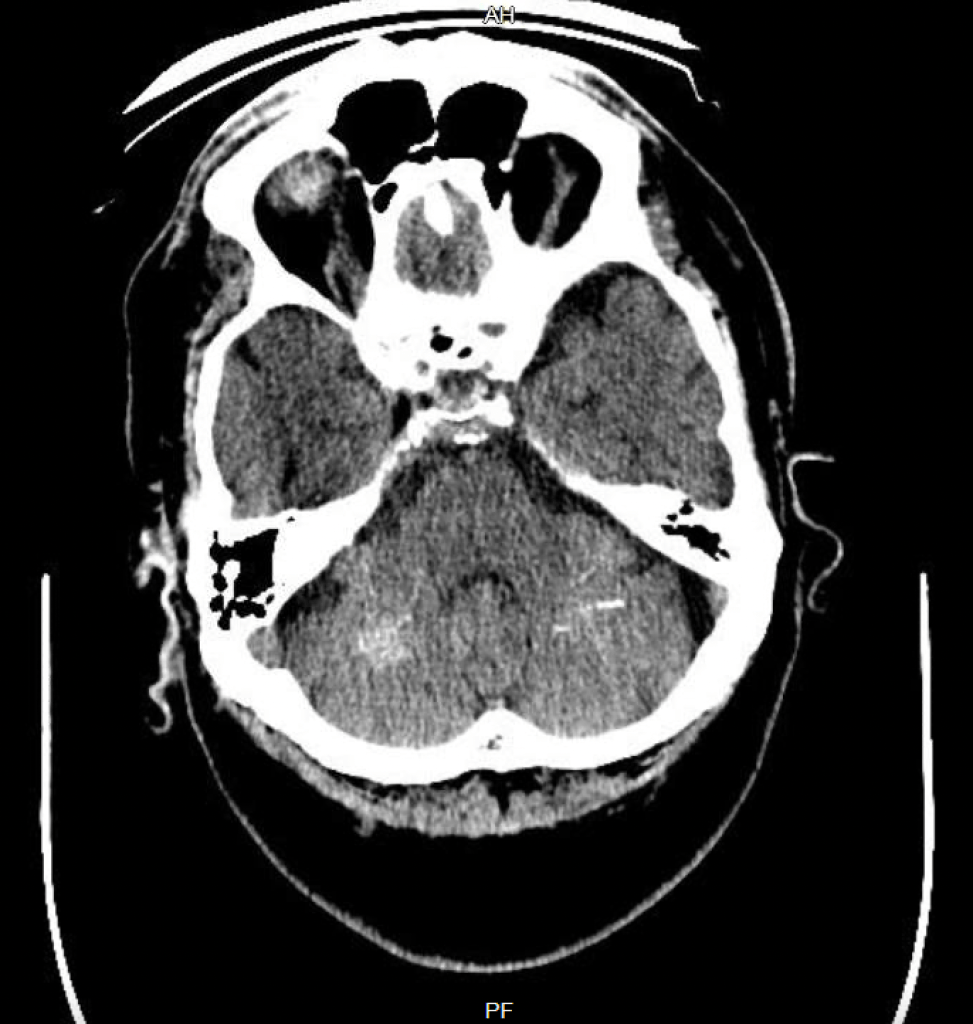

Häufiger als zu Eisen-, kommt es zu Kalziumablagerungen v.a. im Bereich der Stammganglien und des Kleinhirns. Es sind aber auch andere Manifestationsorte beschrieben, z.B. der Thalamus, das Marklager oder auch der Kortex. Diese Ablagerungen sind – in wenig bis mäßig ausgeprägtem Ausmaß – gar nicht selten (2-10% der Fälle in bildgebenden Reihenuntersuchungen) und häufig asymptomatisch. Symptomatische Formen sollen mit einer Häufigkeit von etwas über 1:1.000.000 auftreten. Theodor Fahr hat diese Krankheit 1930 erstmal beschrieben. Theodor Fahr ist von den drei deutschen Pathologen, um die es heute gehen soll und die alle in die Kategorie alte Nazis fallen, vermutlich noch der unproblematischste. Das ist wohl auch der Grund warum – anders als bei der Neurodegeneration mit Eisenakkumulation im Gehirn – noch der Eigenname für die Krankheit verwendet wird. Synonyme, die man aber auch ab und zu findet sind: Idiopathische Stammgabglienkalzifikation, striopallidodentale Kalzifikation.

Einfach ist der Morbus Fahr in der CT zu diagnostizieren, aber auch in der MRT kann man die Stammganglienkalzifizierungen mit einer Signalabsenkung in der T2 und hypo- aber auch hyperintensen T1-Veränderungen recht einfach feststellen.